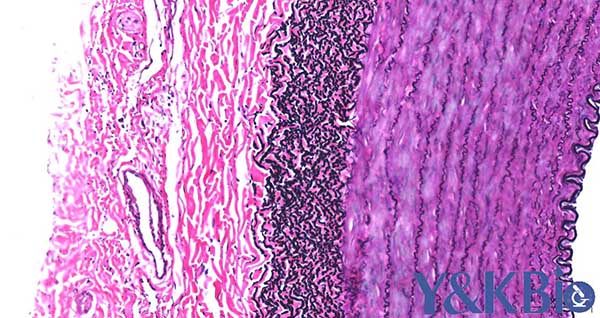

六、movat五色法

适用于血管、心脏、石蜡切片, 同时观察弹力纤维,胶原纤维,蛋白聚糖

染色结果:蛋白聚糖蓝色,肌纤维浅红色,纤维素深红色,弹力纤维和细胞核紫黑色,胶原蛋白和网状纤维黄色